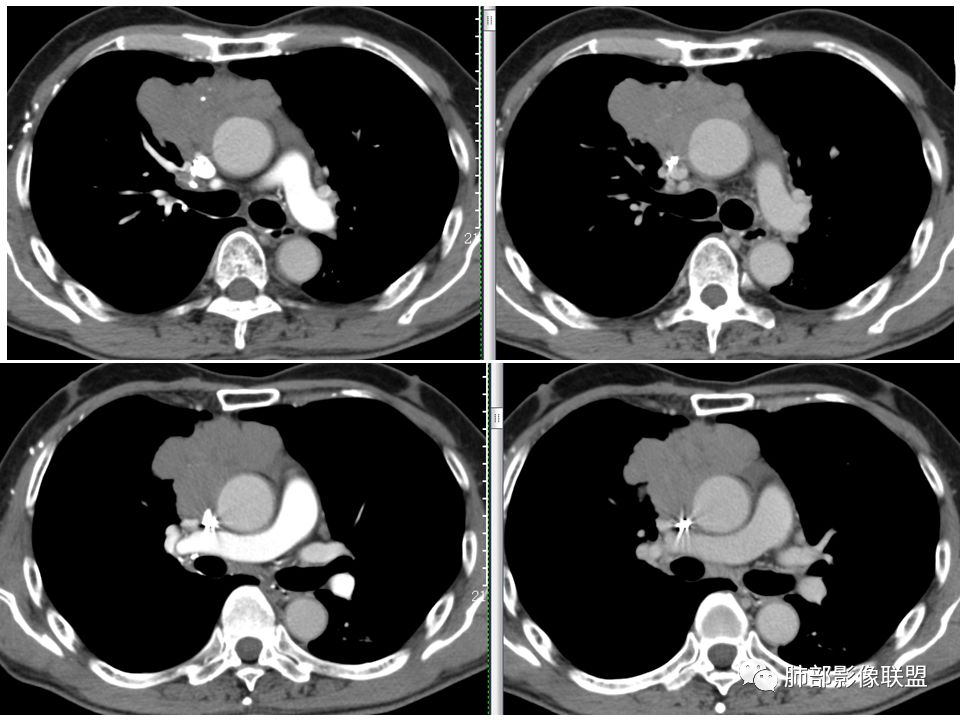

马春平(张家港市一院胸外科): 老年男性,前纵隔占位,中央细沙钙化,右上支气无阻塞,均匀强化、分叶,与心包广基接触,纵隔鳞癌>胸腺瘤

哞: 上腔侵犯,考虑侵袭性胸腺瘤,或者癌

红星: 定位前上纵隔占位性病变,考虑侵袭性胸腺瘤

一切∮随缘: 病灶主体位于前纵隔,向主动脉周围蔓延,与周围组织间隙清楚,病灶形态较软,与胸膜交界尚可,部分支气管受压截断,平扫密度欠均匀,内部可见低密度钙化,增强后轻度均匀强化,坏死不明显,考虑:1:畸胎瘤2:胸腺瘤3:淋巴管瘤

小兜:老年男性,受凉后发烧就诊,前上纵隔不规则肿块,分叶,内见结节状钙化,包绕上腔静脉及左头臂静脉,挤压右肺,增强后轻度强化,内部可见多发低密度区,双侧内乳血管未见明显增粗?考虑为恶性,胸腺癌可能

张小兵: 前纵隔不规则肿块,分叶、包绕血管,内见点状钙化及裂隙样低密度区,轻度强化,倾向恶性,胸腺癌可能,鉴别淋巴瘤。

王秀仙: 前纵隔占位,边缘结节状分叶,多发沙粒状钙化,内部见裂隙状分隔,周围肺组织推移,与心包广基接触,中度强化,病灶左后方心包内积液,叶间胸膜多发结节,考虑纵隔胸腺瘤B3。

丽: 老年男性,咳嗽发热,前纵隔不规则软组织肿块,与纵隔面呈宽基底,周围脂肪间隙消失,边缘分叶、膨隆,内可见点状钙化,增强后轻度强化,考虑胸腺癌

流心明智: 老年男性,前上纵隔不规则肿块,分叶,中央点状钙化与裂隙样低密度区,上腔受侵,与心包广基接触,轻度均匀强化。考虑:胸腺Ca?鉴别淋巴瘤。

飞鹰行动: 部分图片看不到,前上纵隔占位?看不到肿块与支气管的关系,主动脉前间隙消失,肿块内有钙化,边缘分叶,初步考虑纵隔胸腺来源,胸腺瘤(B2/B3)

三个石头: 前上纵隔占位,形态不规则,内见钙化结节,排除淋巴瘤,肿块内低密度区,大血管周围脂肪间隙消失。内小血管穿行供血。考虑胸腺癌。临床症状可能与肿块压迫右上前段支气管有关。

薇: 前纵隔不规则肿块,分叶、内见点状钙化,轻度强化,部分层面与血管分界不清,考虑侵袭性胸腺癌,鉴别淋巴瘤。

耿耿: 前上纵隔不规则分叶团块,内见点状钙化,增强扫描轻度强化,右肺上叶前段受推压,考虑侵袭性胸腺瘤或纵隔鳞癌

生来征服~浪子: 前纵隔偏心性占位,分叶明显,有钙化及囊变。考虑胸腺瘤

良孑: 定位纵隔,肿物是分叶,内可见低密度坏死及钙化,坏死边界模糊,纵隔内可见肿大淋巴结,血管脂肪间隙受侵,提示已有转移,高龄,肿物分叶并转移,考虑胸腺鳞癌

毛勤香: 右前纵膈肿块,分叶状似结节融合感觉,有粗大钙化和少许坏死,与邻近血管脂肪间隙消失,增强不均匀强化,定性恶性,老年人,胸腺瘤和胸腺癌鉴别。

蓝天白云: 定位右前上纵隔,瘤肺界面欠清,纵隔面周围脂肪间隙消失,包绕周围血管趋势,其内可见低密度条形影,增强轻度延迟强化,考虑侵袭性胸腺瘤,鉴别淋巴瘤

doctor: 老年男性,前上纵隔肿块,分叶,轻度强化,周围似乎有多个淋巴结,考虑胸腺癌?

宇宙: 前纵隔胸腺区偏右侧不规则肿块,分叶,可见钙化,明显凸向右肺内,与大血管间脂肪界面消失,轻中度强化,可见纤维分隔,未见明显转移,考虑侵袭性胸腺瘤或胸腺癌,鉴别淋巴瘤

瑶瑶: 前纵隔肿块,偏向一侧,有分叶,点状钙化,似有分隔,轻中度强化,考虑侵袭性胸腺瘤。

前纵隔分叶状软组织团块,包绕血管,周围脂肪间隙消失,其内可见钙化,增强扫描轻中度强化。首先考虑侵袭性胸腺瘤,不除外纵隔型肺癌。